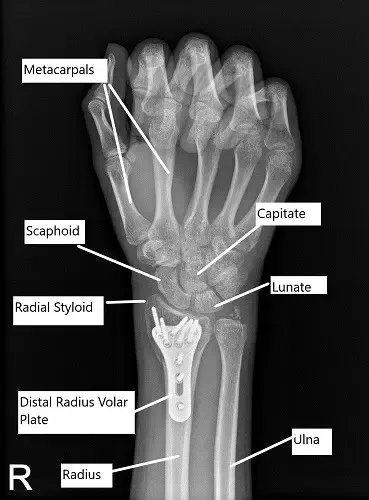

Radiografía postoperatoria de la muñeca derecha en vista de PA.

Al encontrar la fractura y la placa en una posición aceptable, el fragmento distal fue fijado usando tornillos de bloqueo, incluidos dos tornillos estiloides radiales. El primer tornillo era un tornillo cortical para tirar de la placa hasta el hueso. El tornillo cortical se desperdició al final del procedimiento. El fragmento proximal se fijó mediante una combinación de tornillos de bloqueo y no bloqueo. La fijación final de la placa se comprobó en vistas AP y laterales y resultó satisfactoria.

La transfijación de la articulación radioulnar se realizó mediante hilos K. Las fotos finales se tomaron en vistas AP y laterales y se guardaron. La herida fue lavada y cerrada a fondo en capas usando Vicryl #2-0 y Monocryl #4-0. Se usó dermabond para la piel. El vendaje se realizó con 4 x 4, Xeroform, Webril, férula posterior en el brazo largo y venda Ace. El paciente fue trasladado a Recuperación en estado estable.